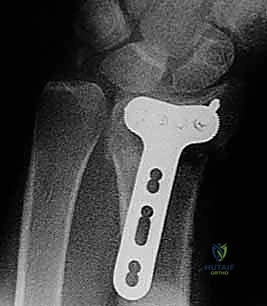

Specialized Medical Category

Operative Techniques in Orthopaedic Surgery